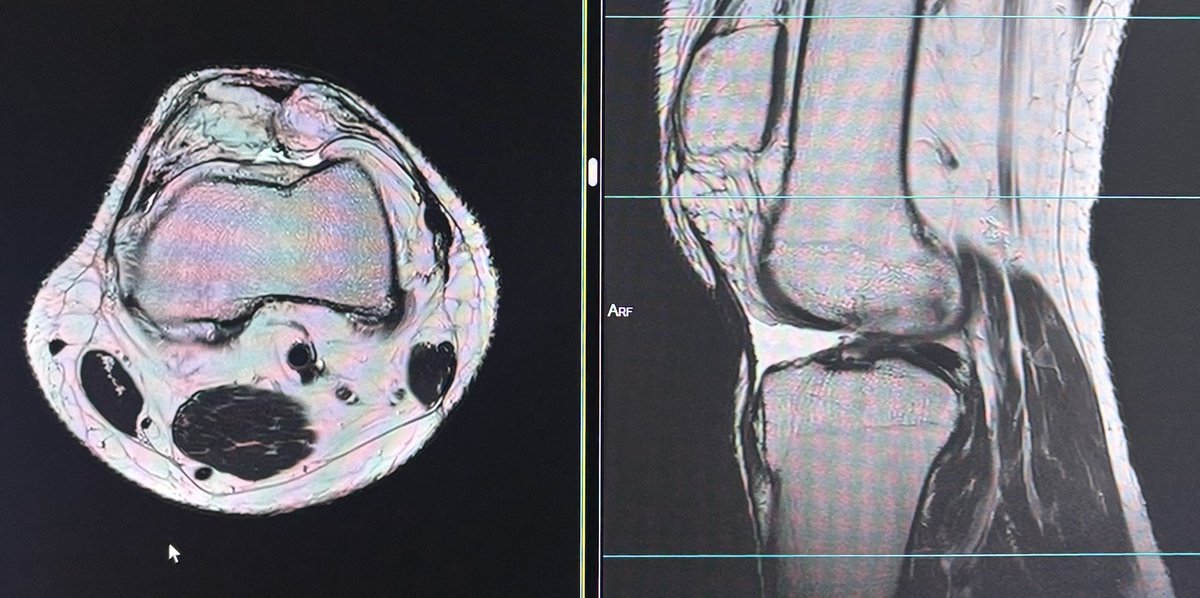

@DrYevSam_Rad Patella alta secondary to chronic patellar tendon tear

36 year old male with hip pain since 20 days.

What is the most likely diagnosis?

#Orthotwitter

#MSKradiology